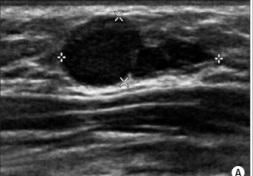

Intraductal papilloma

This condition, also called papillary neoplasm, is a wart-like growth that develops inside a breast duct near the nipple. Usually detected on mammogram, or patient may present with a lump or nipple discharge. It is most common in women aged 35-55. Further testing is required to exclude breast cancer. Single papillomas with no abnormalities do not increase a women’s risk of breast cancer, but those with papillomatosis (multiple papillomas) have a slightly elevated risk. Regular surveillance is advised for this cohort.

Diagnostic value of 3D fast low-angle shot dynamic MRI of breast papillomas. by E. J. Son, E. K. Kim, J. A. Kim, J. Y. Kwak, J. Jeong is licensed under CC BY-NC 3.0